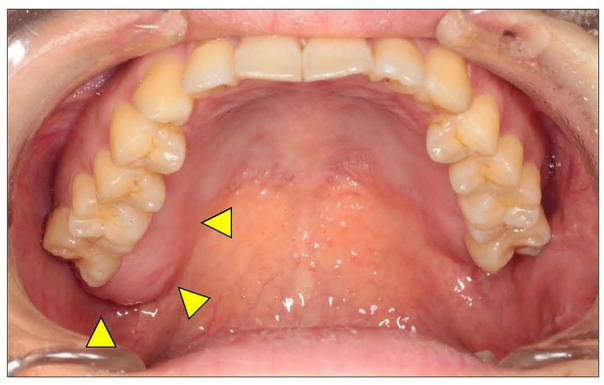

Aim/objective: Mucosal neuroma (MN) is a benign peripheral nerve tumour that usually occurs as a symptom of multiple endocrine neoplasia type 2B (MEN2B) (MEN2B-associated MN). MN that is not associated with MEN2B is termed solitary mucosal neuroma (SMN). We present a case of SMN in the upper gingiva and examine previously reported cases.

Results and conclusion: SMN is thought to be caused by the overproduction of nerve growth factors due to trauma or chronic continuous stimulation, whereas MEN2B-associated MN is caused by GNDF-induced hyperplasia. Considering the pathogenesis of their development, both diseases exhibit hyperplasia of the nerve fibre bundles and have the same histological type of hypertrophy. MNs (SMN and MEN2B-induced MN) must be differentiated from benign peripheral neurogenic tumours. Morphological recognition and immunohistopathological analyses make this differentiation possible.